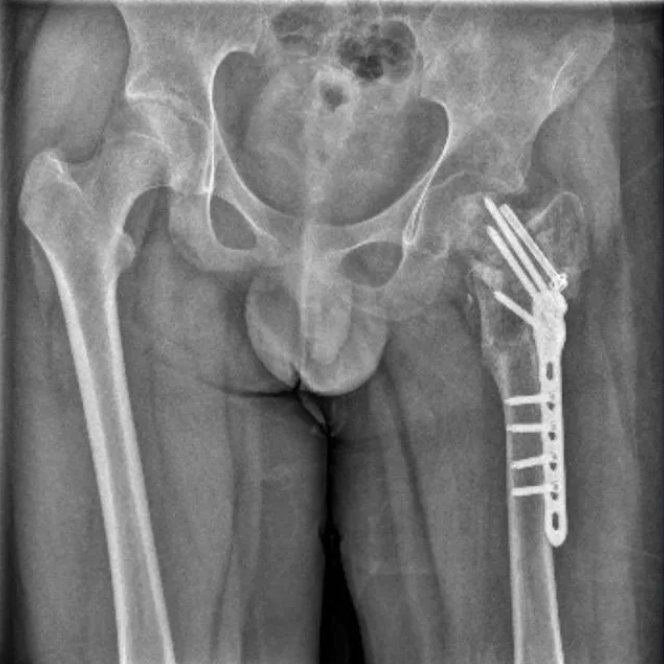

2023年6月和8月,来自北方某城市的武女士先后把14岁的双胞胎儿子大武和小武送到四维成长基地,接受所谓的“半军事化训练”。然而,小武却在28天里遭到各种虐待,身上多部位有“深坑”样伤口,多处感染,最终“左髋部重伤二级、胸部轻伤一级、双下肢轻微伤”,至今仍处于半残疾状态。